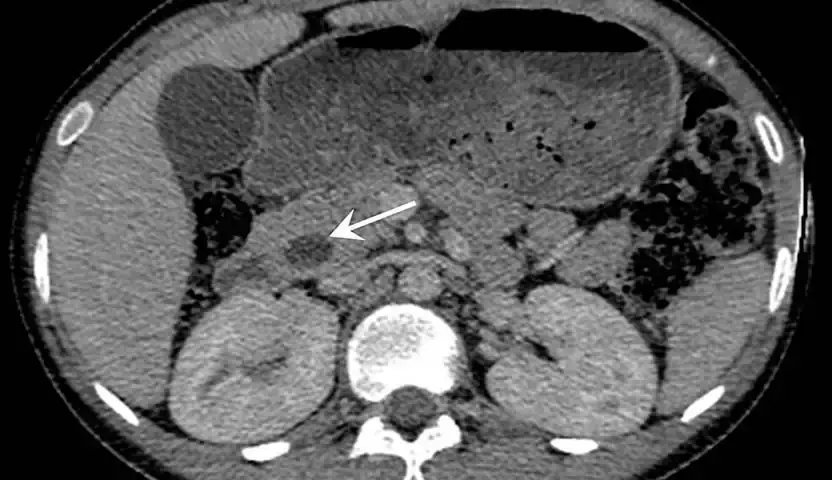

• الفحوص التصويرية: تشمل مجموعة من الأدوات التي تُستخدم لالتقاط صور دقيقة للجسم؛ لتحديد موقع السرطان وحجمه، كما تساعد في معرفة ما إذا كان السرطان قد انتشر إلى مناطق أخرى خارج أمبولة فاتر، ومنها التصوير المقطعي والتصوير بالرنين المغناطيسي.